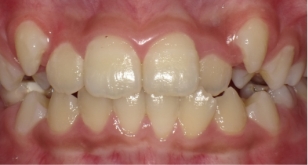

伊藤矯正歯科医院での安定した症例

これに対し伊藤矯正歯科医院では、抜歯を伴う矯正を行ったのちに何も装置を使用しなくて何年か経過しても、かなり安定している症例をみることが多くありました。(「安定調査症例1~4」と当HPの症例集ページ「叢生第3,4症例」をご覧下さい。)そこで治療が終わって数年経過した時点で、資料採得のできた14症例について歯並びの変化を観察しました。